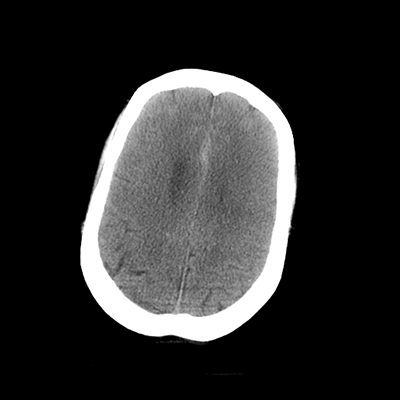

NCHCT

In terms of her neuroimaging, it's clearly abnormal. With the non-contrast head CT, we can see an acute SAH, with blood in the basal cisterns and Sylvian fissures, with some trace blood in the ventricles. The ventricles generally don't look too large, but actually, the temporal horns and atria are visible and larger. So, there's definitely ventriculomegaly that, in combination with her clinical exam, suggests hydrocephalus.